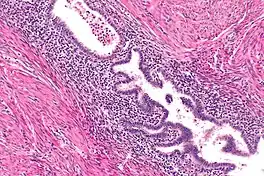

Gallbladder adenomyomatosis is a benign disease of the gallbladder characterized by hyperplasia of the mucosal epithelium and smooth muscle cells inside the muscularis propria.[4][5][6] The excessive proliferation of epithelial cells causes the mucosa to invaginate into the muscular layer lining the gallbladder wall, resulting in characteristic diverticula known as Rokitansky-Aschoff sinuses. These sinuses may be filled with biliary sludge, cholesterol crystals, or gallstones.[4][5][6]

There are three morphologic variants described in the literature – diffuse, segmental, and localized.[5][6] Diffuse, also known as generalized, adenomyomatosis has a widespread distribution of hyperplastic changes and thickening across the gallbladder wall.[5][6] The localized form of adenomyomatosis is also known as a gallbladder adenomyoma (in a similar manner that uterine adenomyoma is the localized variant of adenomyosis). The localized form is a single mass, typically in the fundus, that protrudes into the lumen of the gallbladder in the form of a polyp.[5][6] The segmental form is characterized by its annular (ring-shaped) distribution of adenomyomatosis in the body of the gallbladder, often giving it an hourglass-like appearance.[5][6]